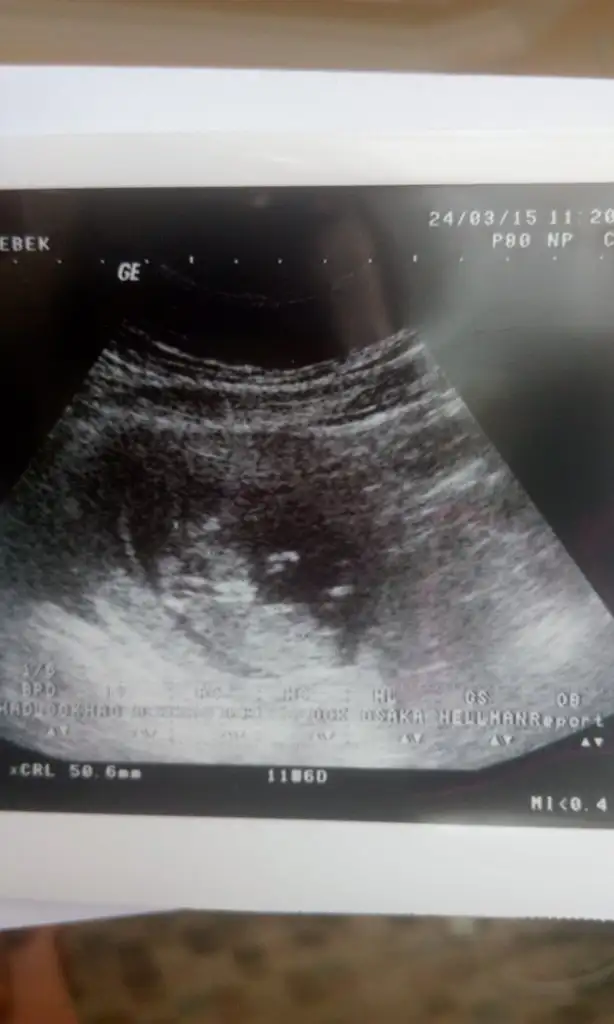

Nubu çizgisini net goremedim erkek gibi geldi baska foto varmi

Zaten bişey görünmüyoki bide özek hastahaneye gidiyoruz ama nerde doğrudürüst bir ultrason resmi bile vermiyorlar bak buda bacak arasımı neresi onuda anlamadım ama biyeri işte ama ölçtüğüyer uyluk kemiği heralde oralardırson fotoya göre kız hissettim, ama birşey gördüğüm için değil, his sadece

Nub cizgisi görünmüyor bir ay daha bekleyeceksin simdi şansızlık olmus gerci iki oğlun varmış farklilik vardır bunda kizsa eger hayırlısi olsun bebisinKızlar bugün gittim ama malesef yine yok ya kordonu tam orayı kapatıyormuş ama bu yapılırmı hiç bi tahminde yapmadı hiç mi bişeye benzetemiyo

Evet bişey görünmüyo zaten ters duruyomuş başıyukardaymış ay çok sinir oldum doktoru nerdeyse dinlemedim diyebilirim 2 dir gidiyorum hep kordon ordan geçiyo diyo hiç mi oynamıyo bu kordon yahuNub cizgisi görünmüyor bir ay daha bekleyeceksin simdi şansızlık olmus gerci iki oğlun varmış farklilik vardır bunda kizsa eger hayırlısi olsun bebisin

Evet otururken poposunun oradan çekmiş gibi işteZaten bişey görünmüyoki bide özek hastahaneye gidiyoruz ama nerde doğrudürüst bir ultrason resmi bile vermiyorlar bak buda bacak arasımı neresi onuda anlamadım ama biyeri işte ama ölçtüğüyer uyluk kemiği heralde oralardır

Hayırlısı artık canım benim çoksağol hayır kız erkek farketmezde insan heves ediyo bişey görüyon almak istiyosun olmuyo artık bir aydaha bekle işin yoksa of of neyse ya Allahın gücüne gitmesin hakkımızda hayırlısi vardır onunda bir zamanıEvet otururken poposunun oradan çekmiş gibi işteçıkıntı görünmüyor ama pek net görünmüyor zaten bölge genel olarak yine de kız gibi hissettim ben ya, hayırlısı olsun, sağlıkla gelsin de..

Canim bu bebek erkek bence cok tatli tipe bakDecember. Melek . Sebahat kizlar hepiniz bide biz bebise yor yapin kuzenimin bebise bi bakin sizce neyy